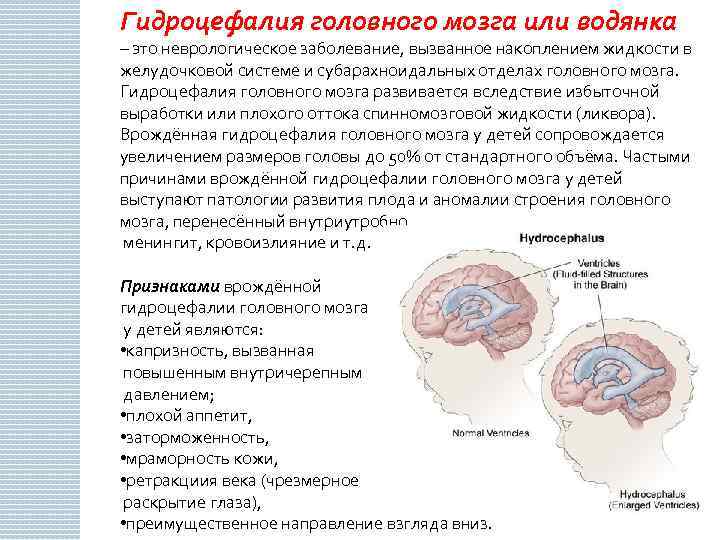

Признаки умеренно выраженной наружная

Признаки умеренно выраженной наружная 113 фото